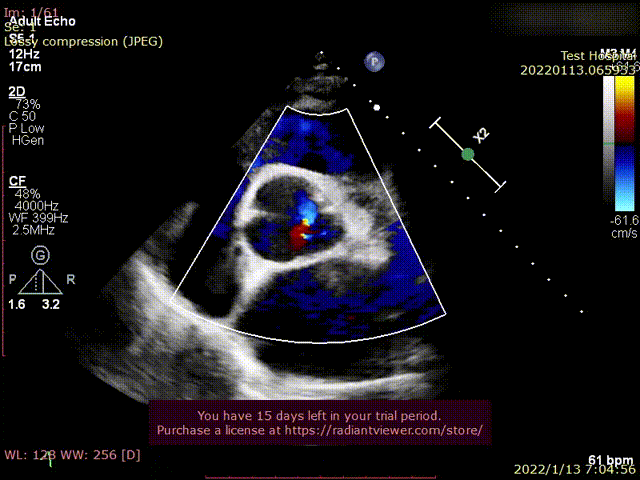

患者为68岁男性,因“活动后心累,气紧半年,加重1周“主诉入院。术前超声提示全心增大,左室肥厚,LVDD 75mm ,LVEF 48%,主动脉瓣重度反流。术后即刻主动脉瓣大量反流消失,LVDD 59mm,左室较术前显著缩小。

术后超声1

术后超声2